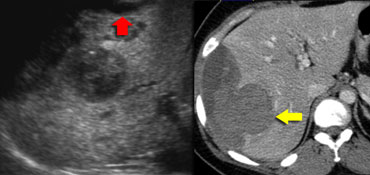

Small hemangioma atypical on US, showing typical enhancement of small hemangioma on CT. Small hemangioma atypical on US, showing typical enhancement of small hemangioma on CT.

On the left an atypical hypoechoic lesion, surrounded by a small but definite halo.

In the arterial phase there is homogeneous enhancement of arterial intensity, frequently seen in small hemangiomas.

In the portal venous phase and in the equilibrium phase it has the same enhancement as the aorta.

So all appearances are consistent with a hemangioma, a benign, non-solid vascular lesion.